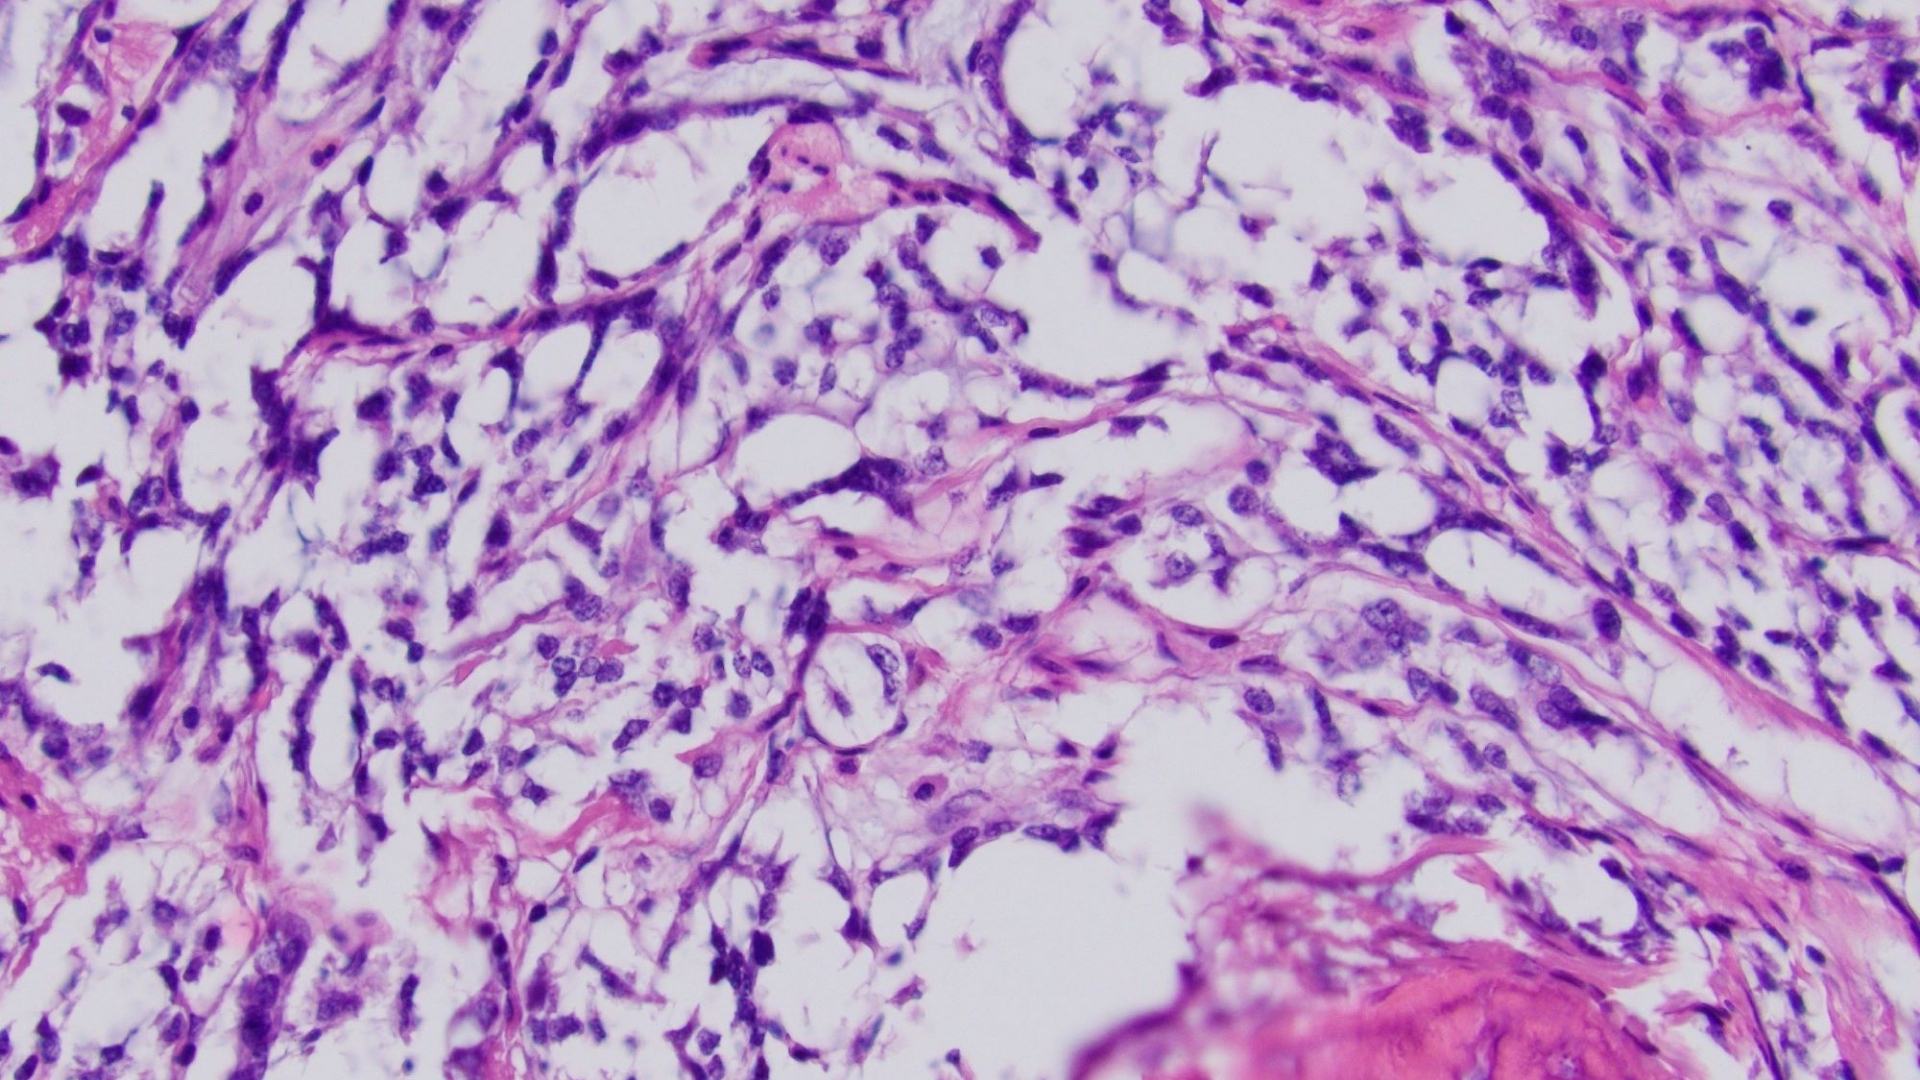

A Gastrointestinal Stromal Tumor (GIST) is a rare form of cancer characterized by abnormal cells in the gastrointestinal (GI) tract, primarily arising from specialized nerve cells called interstitial cells of Cajal. These cells regulate digestive movement and play a crucial role in gut health. GISTs predominantly affect the stomach and small intestine but can appear anywhere along the digestive system.

GIST tumors are commonly driven by mutations in the KIT or PDGFRA genes, responsible for encoding receptor tyrosine kinases (RTKs). Upon mutation, these proteins are uncontrollably activated, causing excessive cellular growth and division. Comprehensive awareness of these biological factors enhances both patient empowerment and the design of targeted therapeutic approaches.